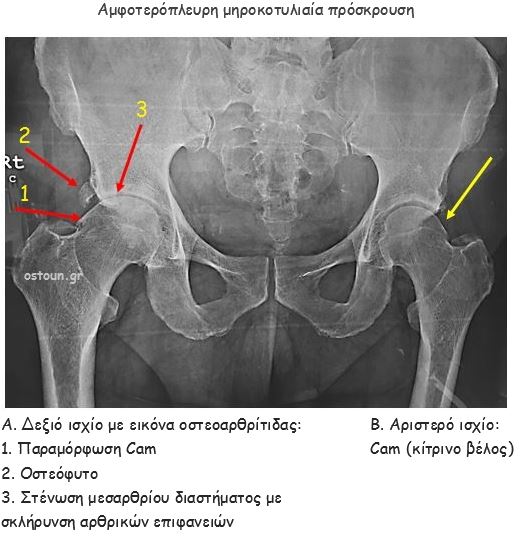

Απεικονιστικές σχολές συνδρομου μηροκοτυλιαίας διακρουσης

Η πάθηση επιβεβαιώνεται με απεικονιστικό έλεγχο. Αυτός περιλαμβάνει:

- ακτινογραφίες,